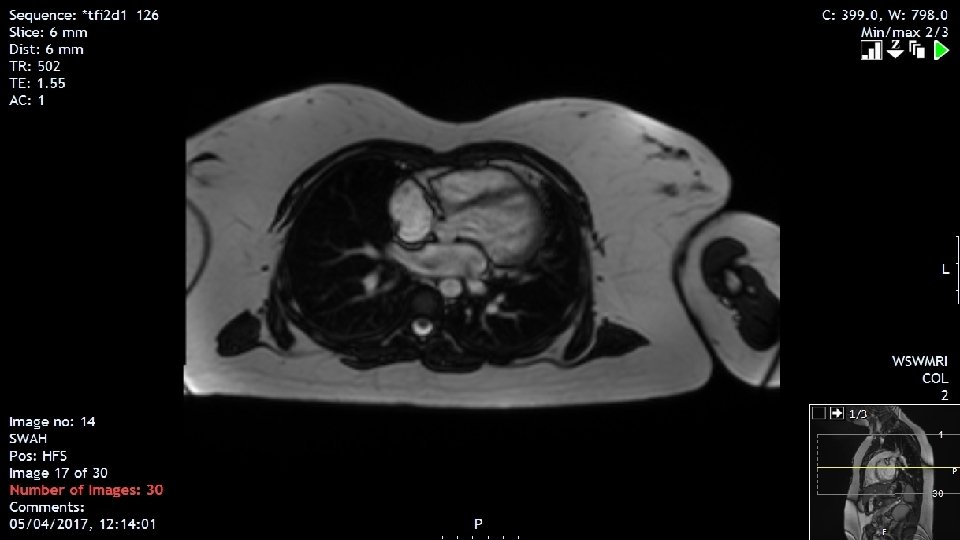

Late Effect: Cardiomyopathy 2004 aged 14 years • Echo RBHSC 10 year post Rx. Normal left ventricular function with a shortening fraction of 29%. Estimated LVEF 65%. Discharged from paediatric cardiology 2016 aged 26 years • Developed SOB on exertion and chest tightness. Non smoker noted to be overweight. Referred to adult cardiologist in RVH with special interest in post chemotherapy cardiac failure. • Echo decreased cardiac function with LVEF of 41%. Cardiac MRI. • Commenced on Ace inhibitor and beta blocker • Heart failure nurse specialist education and lifestyle advice. 2017 • Good improvement in symptoms with cardiac medication

Discussion point • Link to Adult Cardiology service • Previously all follow up by ECHO in RBHSC and results discussed with patient by oncologist at LTFU clinic • Dr Lana Dixon, Consultant Cardiologist, Royal Victoria Hospital • Cardiologist with special interest in heart failure • expression of interest in cardiomyopathy in patients previously treated with chemotherapy and radiotherapy • Improved imaging with cardiac MRI – much more sensitive than ECHO